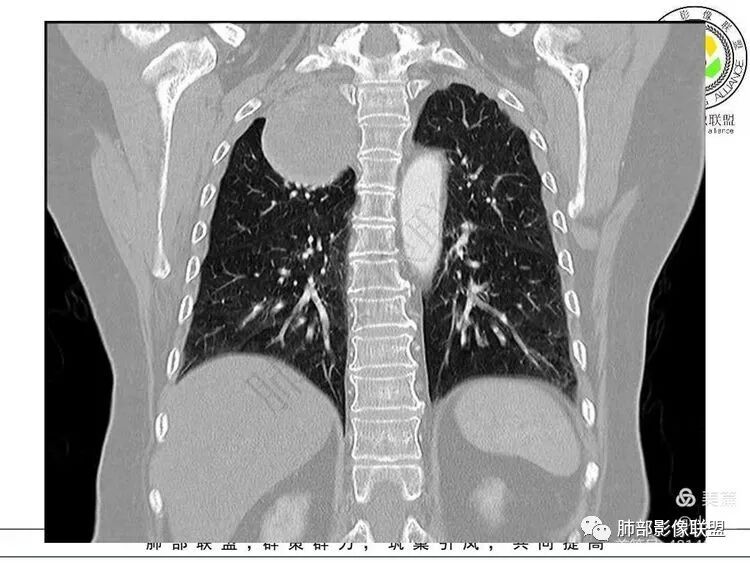

肺侧边缘光滑,D字征,肺血管受压外移肺外没问题

血管、压缩肺组织病灶的长轴:上下走形

1. 右上胸廓入口区类椭圆形块影,边界清楚光整,纵向“嵌顿”于颈根部及上纵隔,向上推移右锁骨下动静脉,向外下方推移上肺胸膜及肺组织(肺血管、支气管),向前推移上腔静脉,界限清楚。

神经鞘瘤是周围神经最常见的肿瘤,起源于神经鞘膜的施万细胞,生长缓慢,包膜完整,与起源神经紧密相连,绝大多数为良性,恶性罕见;纵隔内神经源性肿瘤90%发生于后纵隔,发生在交感神经链或肋间神经的椎旁;偶尔,神经鞘瘤可位于中纵隔或前纵隔,最常见的发生于迷走神经,其次是喉返神经、膈神经等。所以神经源性肿瘤很重要一点在于解剖,一般只要存在神经组织,都可以发生神经源性肿瘤;后纵隔神经鞘瘤最常见的位置是脊神经刚出椎间孔的位置,并沿着肋间神经分布,所以一般横径大,上下径小,而且来源于神经根的可呈哑铃状跨越椎管内外生长;而来源于前或中纵隔神经的迷走神经或喉返神经等是上下走形,所以神经鞘瘤常表现为上下径长;神经鞘瘤在病理上包括A区和B区,Antoni A区富含细胞,密度较高,Antoni B区含有较多粘液成分,密度较低,可见囊变、出血,如果出血,血肿可见机化、钙化。

后纵隔神经鞘瘤(肋间神经走形,左右径大于上下径)

中纵隔神经鞘瘤(迷走神经走形,上下径大于左右径)